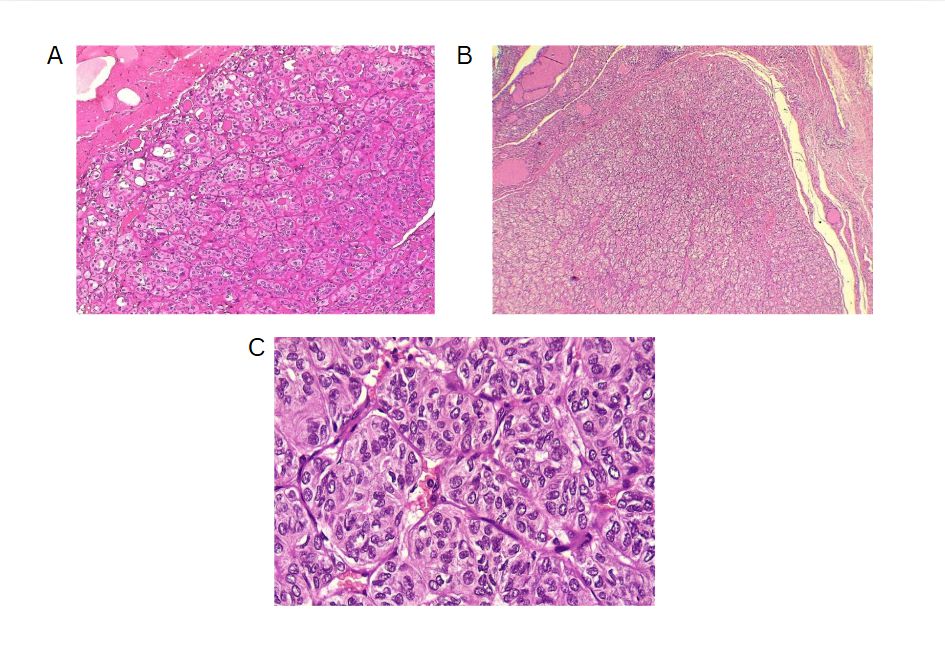

The left thyroid lobe was involved in five cases (45.5%), the right lobe in four cases (36.4%), and the isthmus in two cases (18.1%). The primary surgical approach was total thyroidectomy in seven cases (63.6%), including one patient who underwent concurrent neck dissection (Table 2). Tumor size ranged from 0.5 to 5.5 cm, with a mean size of 2.6 cm (Table 3). All the diagnoses were made post-operatively through histopathological examination (Figure 1).

On gross examination, HTT typically presents as a solid, well-circumscribed mass, or less commonly, as an encapsulated tumor, with colors ranging from yellow to tan, opposite to PTC, which is usually white and does not have a capsule. HTT generally lacks invasion into the capsule, vasculature, or thyroid parenchyma [5,7]. However, Gowrishankar reported a case in which invasion and malignant behavior were observed in HTT [13].